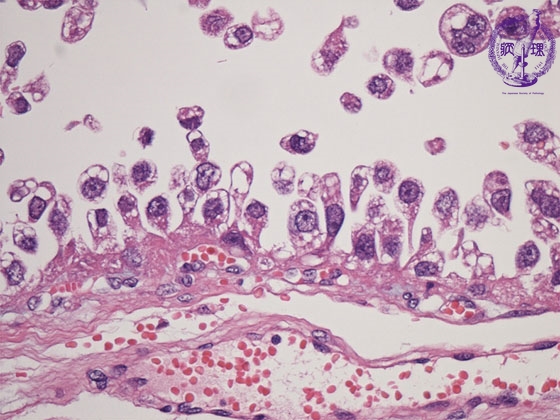

- (8)Clear cell adenocarcinoma of the ovary

Histology (HE stain, high power): Carcioma cells with clear cytoplasm proliferated showing hobnail patterns (nuclei is located at free end of cancer cell as if protruding, red dotted line). The term Hobnail originated from the resembalance between the shape of these cells and the nails with thick head for boot soles.